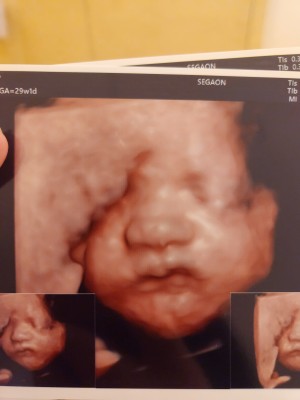

입초 두번째 만에 얼굴보여준 너!

닉네임_윤*영_5

2025-08-22